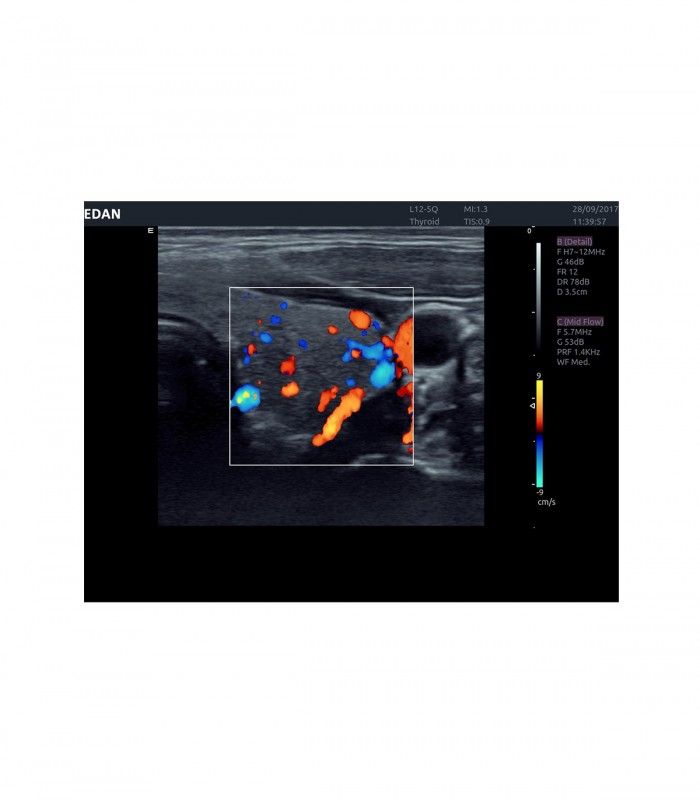

Il est polyvalent dans de nombreux domaines d’applications tels ; obstétrique, gynécologie, urologie, musculo squelettique, cardiologie, vasculaire, abdominal, etc.

L’AX4 affiche une image claire et précise dans les différents modes grâce à de multiple technologies de traitement de l’image.

L’Imagerie Tissulaire Adaptative (TAI) ajuste automatiquement en temps réel de nombreux paramètres, dès la pose de la sonde sur le patient, afin d’afficher la meilleure qualité d’image, permettant ainsi au praticien de poser un diagnostic plus rapidement.

En mode couleur, les préréglages et le TAI automatique temps réel facilitent l’ajustement des flux.

- Imagerie entièrement automatisée (modes B, couleur, doppler, M)